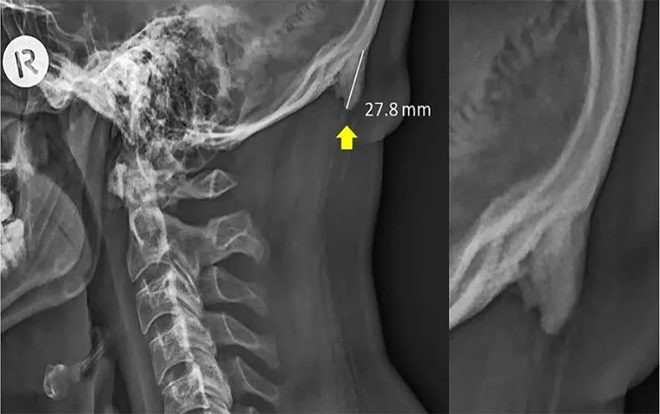

Các nhà nghiên cứu đã tiến hành quét tia X ở hơn 200 người trẻ, tìm thấy các gai xương hay còn được gọi là enthesophytes xuất hiện ở sau đầu. Họ cho biết, hiện tượng phát triển bất bình thường này là do áp lực dài hạn mà bộ xương đã phải chịu vì hành vi nghiêng đầu về phía trước quá lâu khi con người sử dụng điện thoại smartphone trong thời gian dài.

Tiến sĩ David Shahar nói: “Chúng tôi đưa ra giả thuyết rằng áp lực tăng liên tục ở phần cơ sau đầu là do trọng lượng bị dồn lên khi đầu nghiêng về trước để sử dụng các thiết bị công nghệ hiện đại trong thời gian dài”.

“Việc nghiêng đầu về trước sẽ dẫn đến sự dịch chuyển trọng lượng từ xương cột sống tới các cơ sau đầu và cổ”.